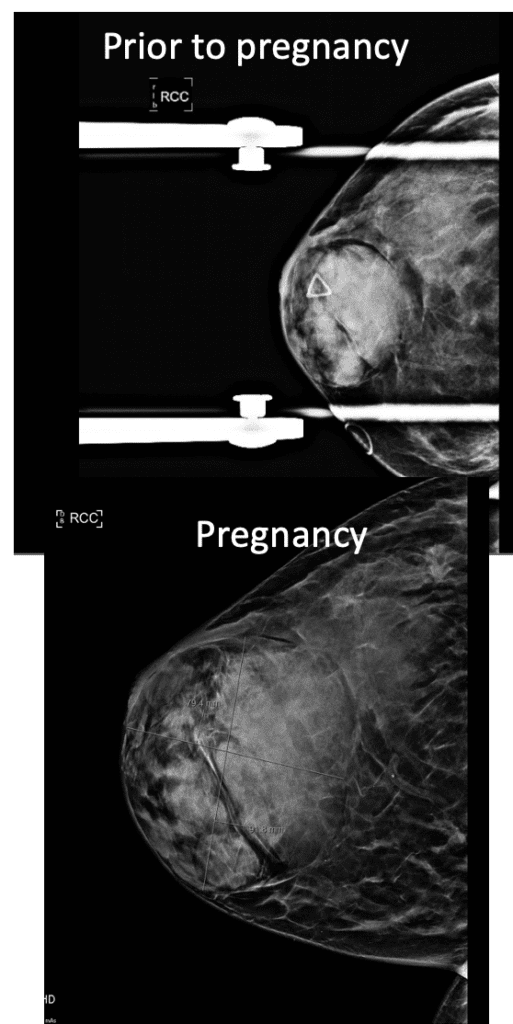

Gestational gigantomastia likely represents a spectrum of excessive breast growth during pregnancy. It may include women who grow multiple cup sizes, or those for whom the breast growth is so significant it can cause mobility impairments. Hormonal factors may play a role in gigantomastia, but true cause remains unknown. It also remains unclear whether the growth represents true glandular development or simply fluid retention in the breast as occurs in other parts of the body during pregnancy. Women gigantomastia that is not significant enough to cause skin breakdown but do experience growth do not necessarily produce large volumes of milk.

During pregnancy, it is treated by bromocriptine (an anti-prolactin agent) alternating with metformin (modulates insulin). Postpartum, patients should be given bromocriptine or cabergoline (anti-prolactin agent) before lactogenesis II (secretory activation, or “milk coming in”) to reduce the risk of skin necrosis (ulceration and death of skin). Donor milk or formula supplementation should be planned. Patients can later undergo elective breast reduction. The patient above is pictured below at end of pregnancy after being treated with lymphatic drainage and bromocriptine during pregnancy:

Improvement in lymphedema with lymphatic drainage and supportive bra/garment, just before delivery. Photo: Clara Farley, MD